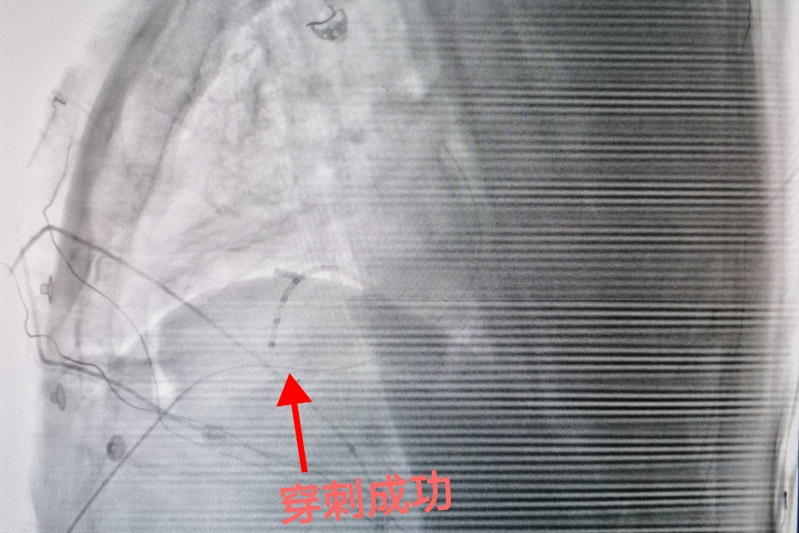

心外膜室性心動過速行射頻消融術這項技術是心包腔內無積液的情況下,經胸壁進行干性穿刺后,將標測及消融導管送到心包腔內,再進行定位消融異常的心電病灶,手術風險大、標測復雜、技術難度高,需要團隊具備極高的心包穿刺及導管操作技術。

為確保手術安全,心血管內科電生理團隊準備了詳盡的手術方案和應急預案。手術當日,北京安貞醫院心血管內科蔣晨曦教授親臨指導,在ICE及X線引導下,精確地將導絲通過心包干性穿刺途徑到達心外膜,再通過動靜脈途徑到達心內膜,采用心內膜聯合心外膜進行標測及消融。放電3秒后室性心動過速終止,鞏固消融120秒,并在靶點附近鞏固放電多次,經過一段時間觀察,無室性心動過速再發,手術順利結束。術后患者癥狀解除,復查動態心電圖顯示無室性心律失常再發,目前陶先生已成功康復出院,門診隨訪也一切良好。